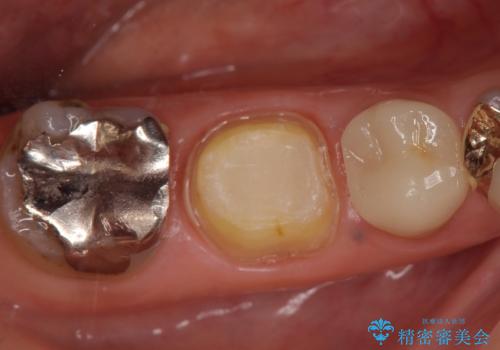

- 右下奥の歯茎がたまに腫れて膿が出るので診て欲しいといらっしゃった方の症例です。

診査の結果右下6の歯の神経が死んでいたため根管治療を行い、オールセラミッククラウンによる補綴を行いました。